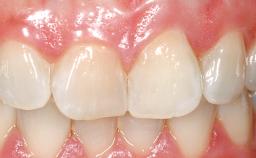

This 43-year-old male patient, a non-smoker, came to our practice because of a fracture of tooth 12 caused by a bicycle accident. Due to the combined para- and infrabony crown and root fracture, tooth extraction, and subsequent implant placement were suggested to the patient as the therapy of choice. The patient had high esthetic expectations with regard to the treatment outcome and asked for an immediate fixed provisional restoration. His individual esthetic risk profile summed up to a medium esthetic risk.

Case Type Single-Tooth Space

Jaw Maxilla

Area Anterior